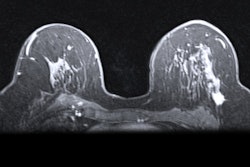

Abbreviated MRI with a short scanning protocol shows potential as a way to screen for hepatocellular carcinoma (HCC) in adults who have cirrhosis or chronic hepatitis B infection, according to a study published November 2 in RadioGraphics.

Abbreviated MRI may also help clinicians better direct treatment of patients with HCC and therefore prolong patients' lives, wrote a team led by Dr. Julie An of the University of California, San Diego (UCSD).

"In the context of HCC surveillance, multiphase abdominal MRI may take approximately 40 minutes to complete and ultrasound may take approximately 30 minutes; whereas, an abbreviated MRI protocol is typically performed in 15 minutes or less and includes only the sequences necessary for detection of HCC," the authors wrote.

UCSD has used the hepatobiliary phase contrast-enhanced protocol since 2013.